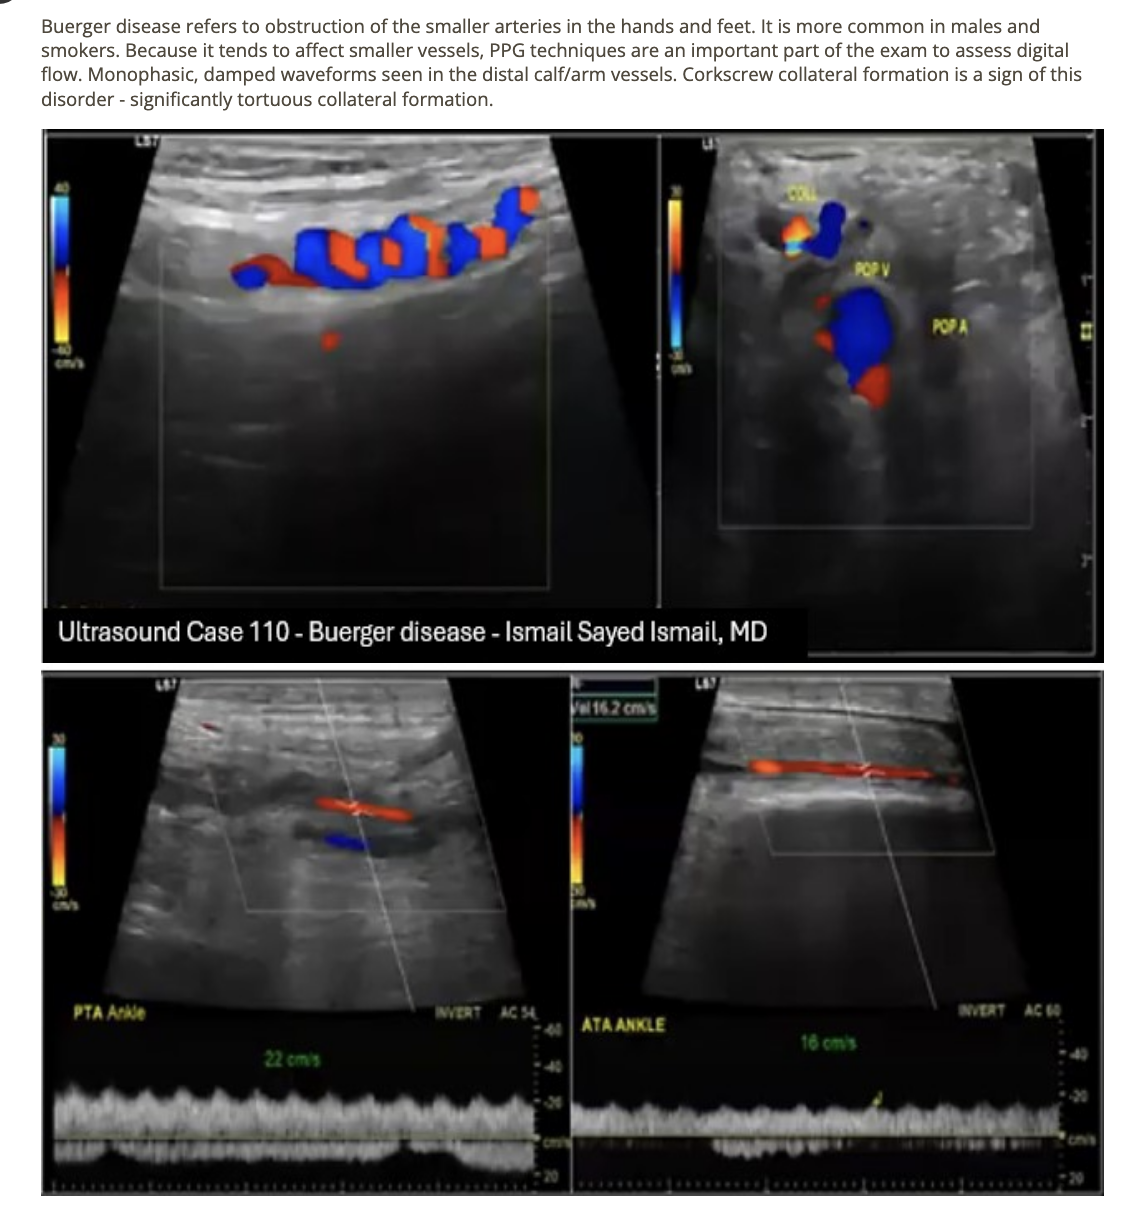

what is the preferred method to rule out Buerger disease in an upper extremity arterial exam? Evaluate the

.

a) shoulder arteries for extrinsinc compression w/movement

b) hands for vascular changes w/cold sensitivity testing

c) smaller arteries of arm w/duplex + PPG

d) arterial flow at rest + exercise

Thromboangiitis obliterans (TAO) where small blood vessels in the hands and feet become blocked by clots. This involves inflammation of

a) intimal + medial wall

b) all vessel walls w/no effect on conective tissue

c) intimal wall layer

d) all vessel walls + surrounding connective tissue